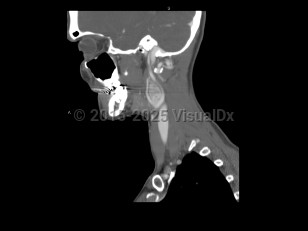

Sore throat, Neck mass, 50-59 year old Female

Peritonsillar abscessPeritonsillar abscess

Retropharyngeal abscess